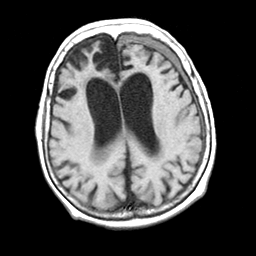

Pick's Disease, MR Study mr-t1 -- Slice #14

[Home][Help][Clinical] Slice 14